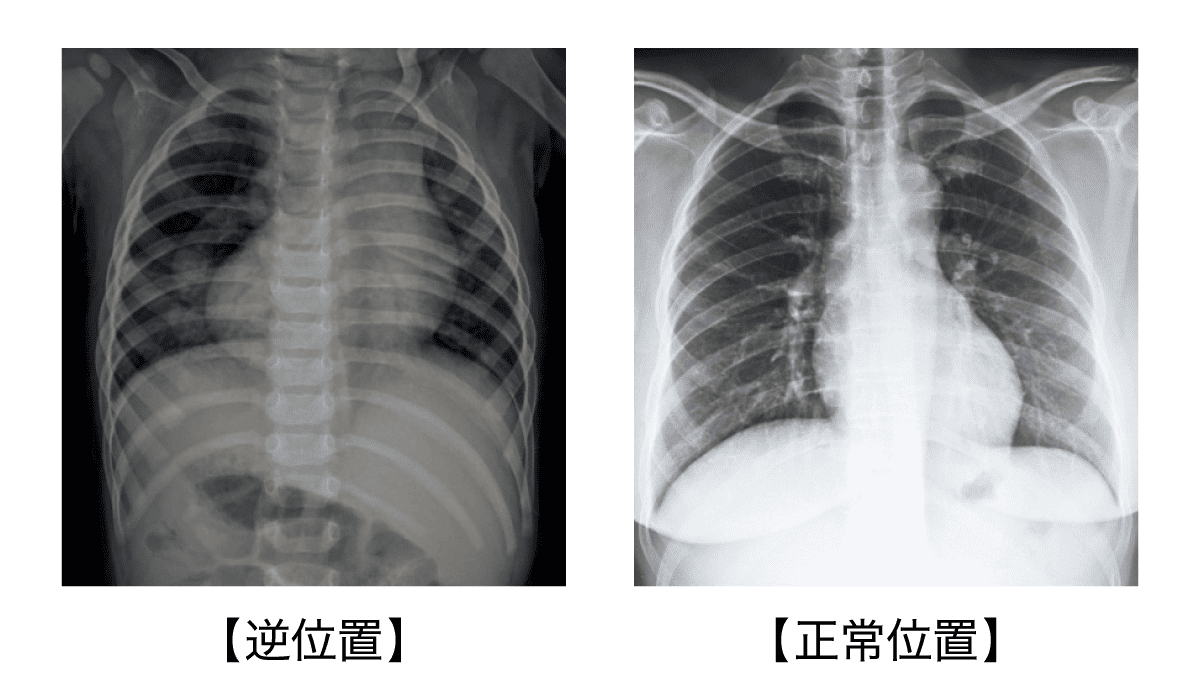

そして心臓血管外科を専門とする花房さんも、研修医時代に内臓逆位の手術を経験したひとり。しかもX線の写真がまだフィルムだった当時、担当の執刀医が表裏を取り違えて、開腹後に逆位が判明したのだという。

「腹部大動脈瘤破裂の緊急手術でしたが、普段と異なる血管の配置のなかでも何とか遮断すべき大動脈を見つけ、手術は成功しました。内臓逆位のケースでは術前の画像確認や手術の手順についてもより慎重に検討する必要があり、専門医による術例の論文も多く発表されています」